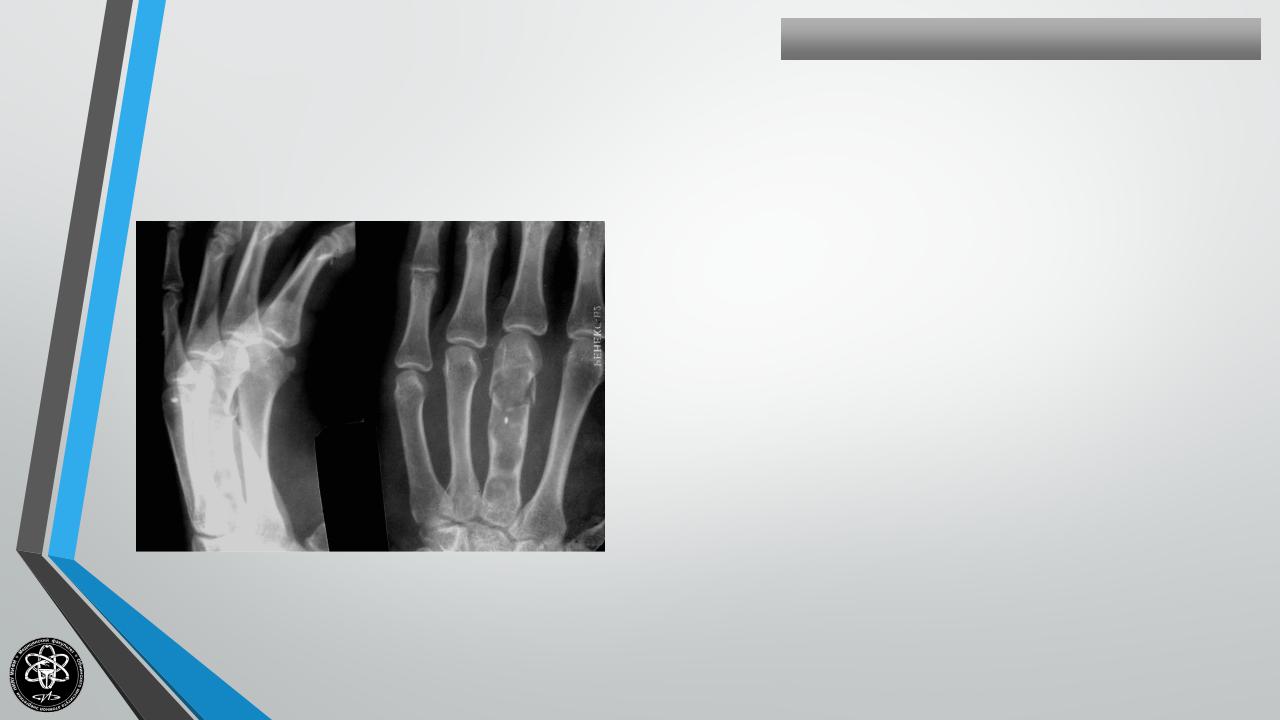

ХОНДРОМА

Частота — 7 ,2 % всех костных опухолей.

Излюбленная локализация — ребра, лопатка, таз, кисти рук, бедренная кость и др.

Поражаемый возраст — 10-50 лет.

Процесс может развиваться в центре кости — энхондрома, или носить краевой характер — экхондрома.

Клиника — боли незначительные или отсутствуют.

Чем старше больной — тем больше опасность малигнизации. В старших возрастных группах малигнизация достигает 90%.

Лечение хирургическое — сегментарная или краевая резекция — в зависимости от формы.

Рецидивы и малигнизация возможны.

К операции предъявляются требования радикальности.